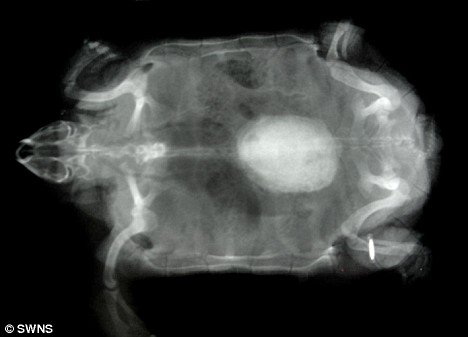

X光顯示波莉體內的結石

獸醫組負責人莎倫·雷德羅塞介紹說,獸醫日前為園內的動物做了例行體檢,當用X光照一只名叫波莉的雌性非洲餅干龜時,醫生們驚奇地發現它體內竟然有一個雞蛋大小的東西,而5歲大的波莉身長才不過5.5英寸(約合14厘米)!

雷德羅塞表示,如果不取出波莉體內碩大的結石,它最終將因腎衰竭而死去。給龜實施麻醉非常具有挑戰性,必須受過專門訓練的獸醫才能進行,但是鑒于波莉已經出現不適,動物園的獸醫還是決定盡快去除它體內的結石。手術共進行了一個小時,獸醫先是在波莉腹部的殼上切開一個洞,然后取出結石,最后再把切開的殼粘合起來。取出的結石重19克,大小為1.5英寸×1.2英寸(約合4厘米×3厘米)。據分析,這塊結石是波莉體內的鈣沉積形成的。